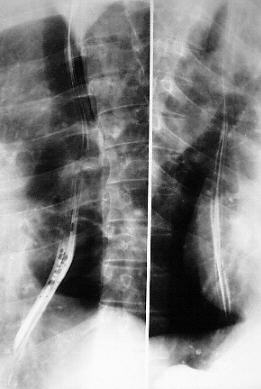

WATER-SOLUBLE CONTRAST SWOLLOW / BARIUM SWOLLOW - ANATOMY

Pathological examples:

Carina

Piriform recess

Aortic arch

Carina of trachea